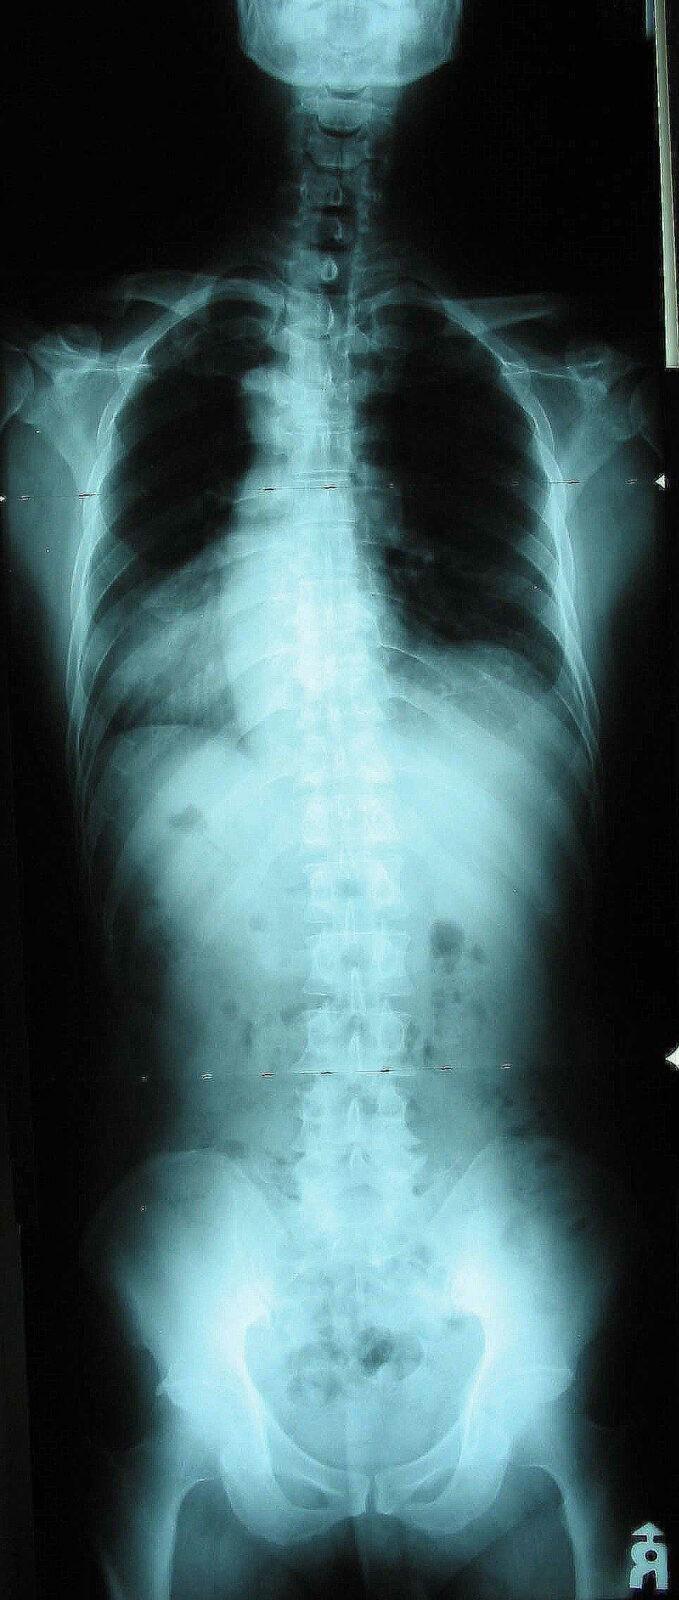

요즘 아이들은 앉아서 공부하는 시간이 많기 때문에 척추의 건강 상태는 점점 더 나빠지고 있으므로 일정 기간 마다 검진을 받는 것이 중요합니다.

모든 치료가 마찬가지이지만 특히 척추측만증은 조기에 발견하면 잘 치료될 수 있기 때문입니다